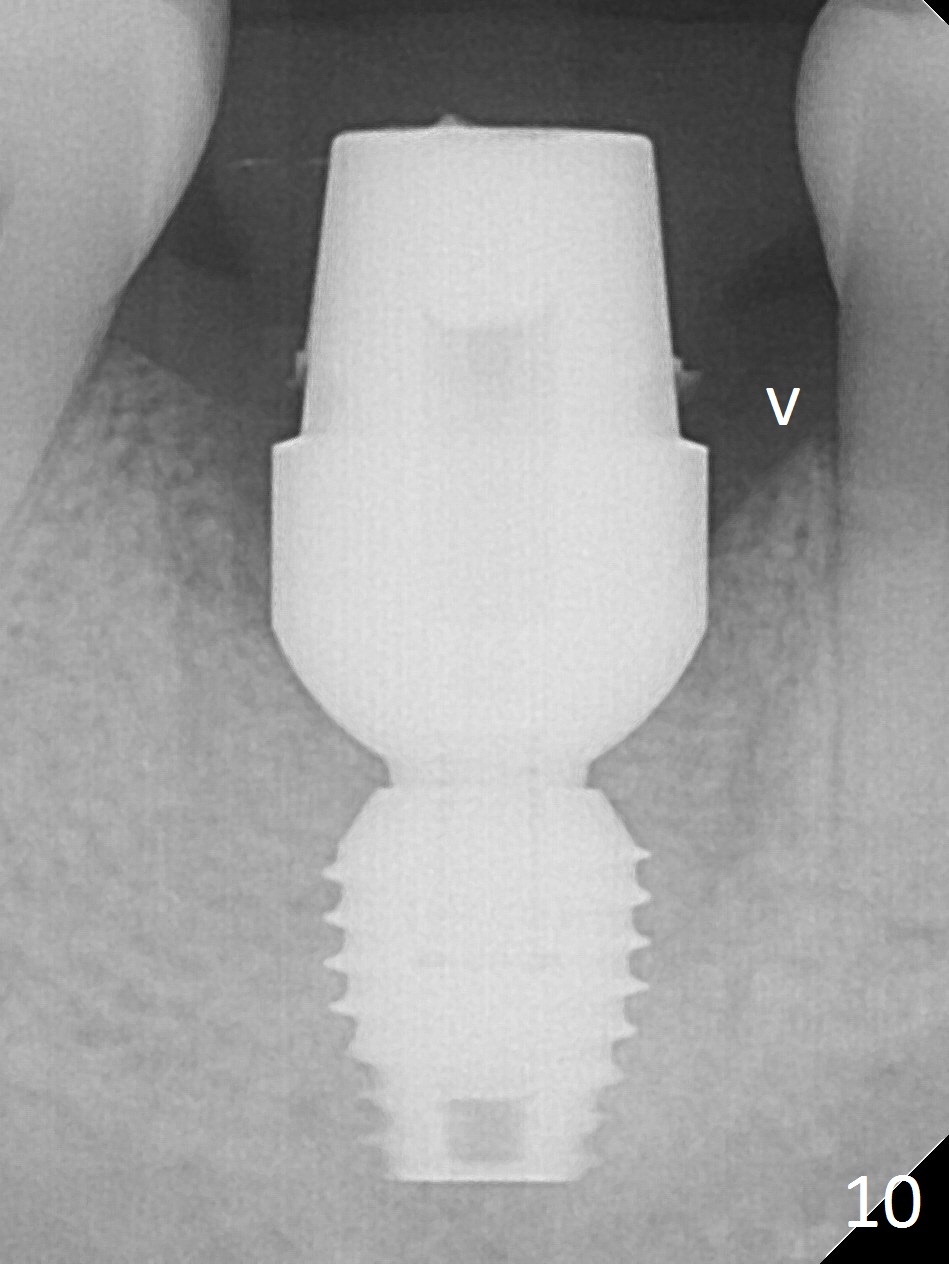

After extraction of the tooth #30 with Class V furcation involvement (Fig.1 (>),2 (L: lingual)), initial osteotomy depth is 8 mm with infiltration anesthesia, but a parallel pin is able to be inserted for 16 mm without pain (Fig.3). There is oozing from the osteotomy. Osteotomy increases in diameter with depth at 8 mm (Fig.4 (3.8 mm drill),5 (5.3 mm tap)). As the Inferior Alveolar Canal (IAC) is indistinct with increased pain during osteotomy, a 5.9x6 mm implant is placed with >50 Ncm following Septocaine infiltration (Fig.6). When bone graft (Fig.7 *) and 7.8x5.5(6) mm abutment (Fig.7,8) are placed, panoramic X-ray is taken (Fig.9). There appears to be a thick layer of spongy bone in the posterior mandible between the red and yellow dashed lines (Fig.5,9). Panoramic X-ray and/or CBCT should be taken if preop PA does not reveal IAC. This patient seems to be a bruxer. There are mandibular tori. Bone loss (furcation involvement) is not proportional to his oral hygiene status. Functional loading (progressive) should be delayed due to bruxism and the short implant.

The bone (Fig.10 arrowhead) and soft tissue (Fig.11 *) heal 2 months postop. Gingivectomy is done with Diode prior to impression (Fig.12). The provisional is relined to keep the margin (Fig.13, 2 weeks later) and a permanent crown tries in (Fig.14).